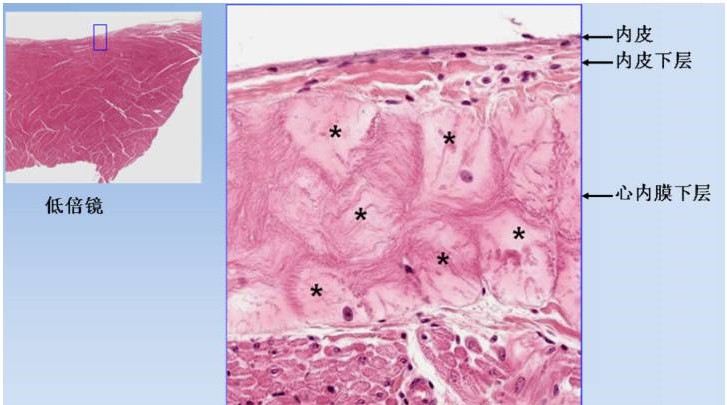

图6. 心壁光镜像,示心内膜和心肌膜。

心内膜分为内皮(1),内皮下层(2)和心内膜下层(3)。内皮为单层扁平上皮,内皮下层为细密结缔组织,心内膜下层中可见浦肯野纤维(*),为特殊的心肌纤维,是心脏传导系统的分支。